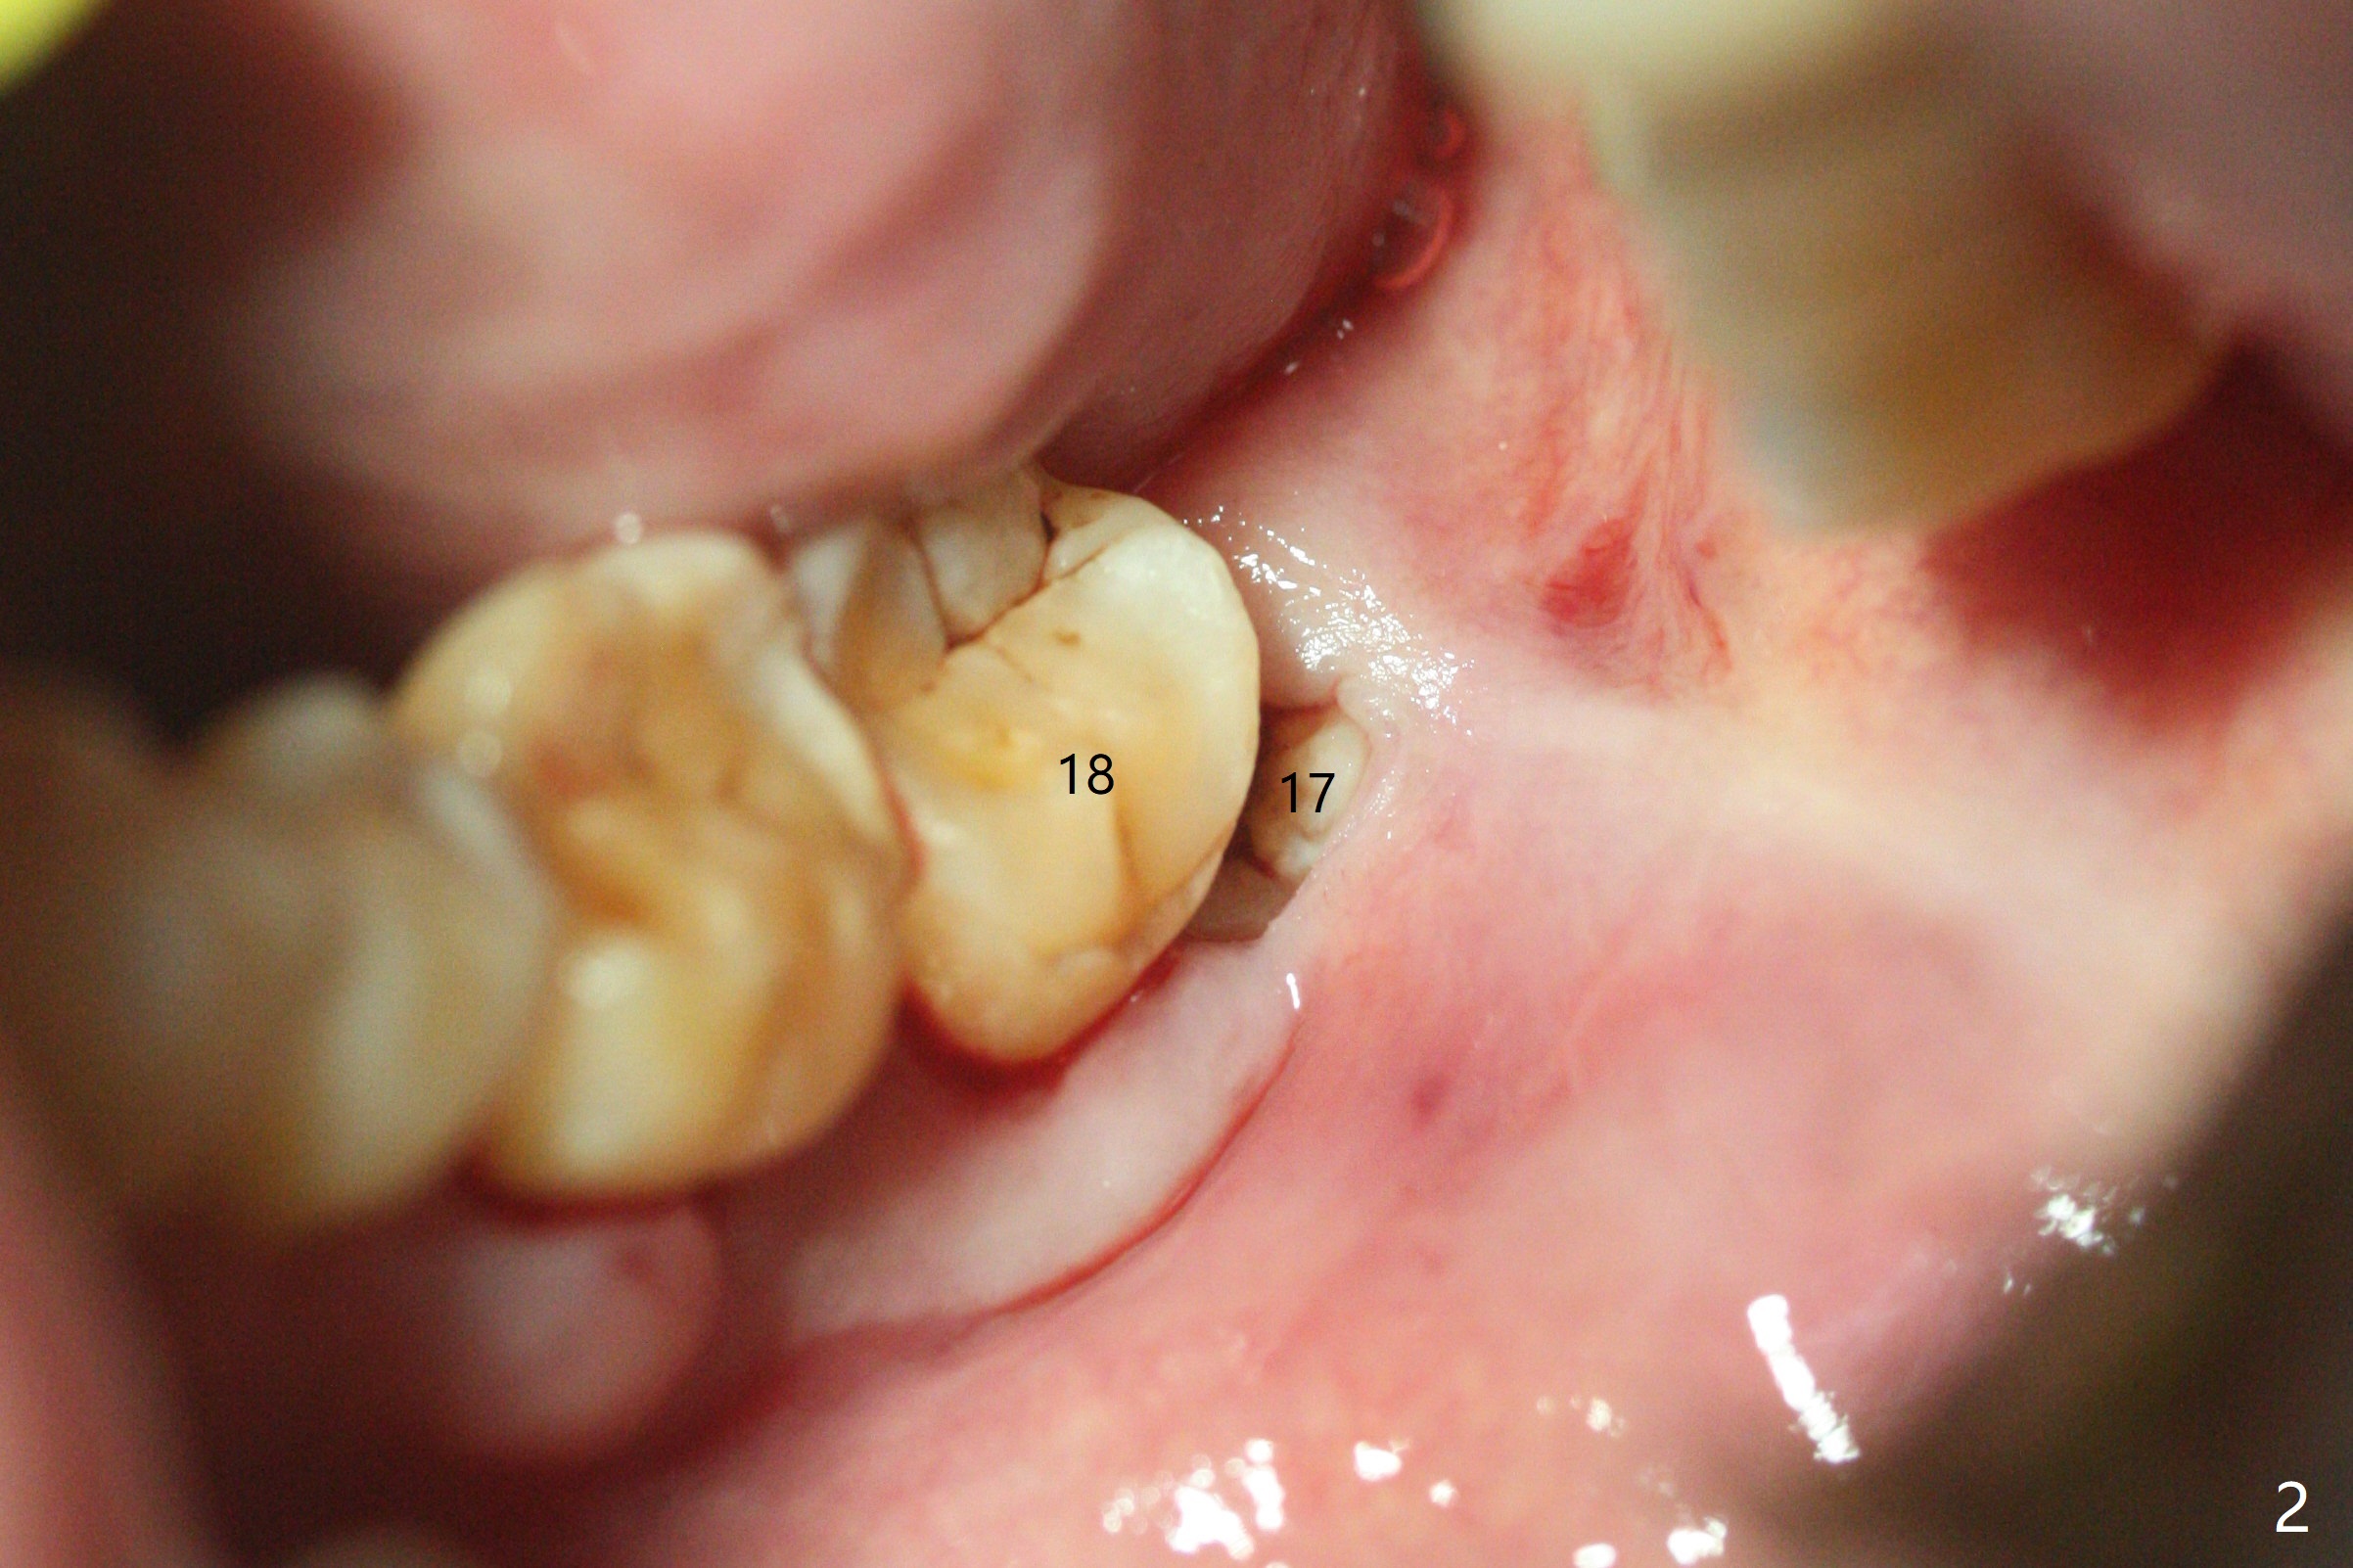

54岁男,吸烟,血糖略微升高,牙周炎,左下智齿疼痛,要求拔除(图一)。由于18号牙近中也有骨质吸收,预后不佳,所以拔除智齿后准备放置胶原塞,防止干槽症。左侧深洗后,发现智齿位于第二磨牙颊侧远中(图二),所以在第二磨牙近中做斜行切口(图三),万一伤口裂开,骨粉流失不会太多。智齿拔除后,发现第二磨牙骨质吸收严重,觉得植骨必要,但是没有时间制备PRF。使用GEM21S与皮质骨骨粉调袢。由于缺损巨大,17号牙牙槽窝远中塞入骨胶原塞(图四:O (Osteogen Plug)),18远中和颊侧放置骨粉(G),骨粉上面放置胶原塞(相当膜的作用),然后缝合。